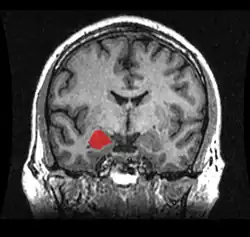

Forschungen an der Universität Wien stellten im Jahr 2015 bisherige Studien zu Erregungsmustern der Amygdala in Frage. Zuvor mittels funktioneller Magnetresonanztomografie generierte Daten, die man für Amygdala-Aktivitäten hielt, stellten wohl nur den Blutfluss in der Rosenthal-Vene dar.[9][10]